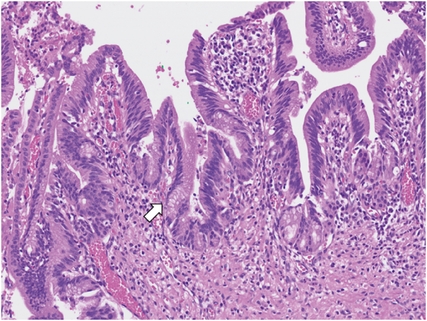

A 7-year-old girl visited the pediatric department of Asan Medical Center for endoscopic retrograde cholangiopancreatography (ERCP) to remove a distal common bile duct (CBD) stone. She was previously healthy and visited a nearby hospital due to abdominal pain and vomiting lasting for 13 days, and jaundice progressed the day before hospital visit. Computed tomography (CT) revealed tortuous dilatation of the extrahepatic bile duct abruptly narrowed in the distal CBD level with several distal CBD stones and anomalous pancreaticobiliary ductal union (APBDU, P-C type). The common channel was measured as 1.9 cm in length. These findings suggested type I CC related to APBDU. Secondary cholecystitis, cholangitis, and pancreatitis were additionally found (Fig. 1A). The same findings were confirmed on magnetic resonance imaging (Fig. 1B). After failure of the first ERCP at the previous hospital, she kept non per oral for one week, but symptoms and lab findings were never relieved (Table 1). So, she was determined to transfer to Asan Medical Center. ERCP was performed. Both pancreatic and CBD were successfully cannulated, and a 10 Fr. Endoscopic retrograde biliary drainage stent was retained in the bile duct for remnant stone excretion. No residual stone was found in follow-up CT in 3 days post ERCP (Fig. 2). Serum levels of liver enzymes, bilirubin, and amylase/lipase decreased to the normal range. Two months later, robotic CC excision and Roux-en-Y hepaticojejunostomy were performed. Severe adhesion and fibrosis around the CC reflecting chronic inflammation were noted. Type I CC was identified, and CBD was resected proximally above the cystic duct and distally at the upper border of the pancreas head. The patient recovered without acute complications. In ultrasonography of post-operative day (POD) 7, no abnormal finding was observed except a small fluid collection around hepaticojejunostomy. She was discharged on POD 9. In the permanent biopsy, edematous mucosal change of gallbladder (GB) and cystic duct was observed, but the diameter of the cystic duct was within the normal range (0.4 cm). In microscopic findings, papillary hyperplasia was identified. The resected CC was 2 cm in length and 2 cm in the widest circumference. It was pathologically confirmed as a CC, accompanying fibrosis and wall thickening changes of CBD, and low-grade BilIN was identified from the resected CC (Figs. 3 and 4). Papillary hyperplasia in GB suggests chronic inflammation in the biliary system due to CC such as BilIN. There was no involvement in the cystic duct and GB as in Type VI.

Fig. 4

Representative microscopic image of low grade biliary intraepithelial neoplasia (arrow) (hematoxylin and eosin staining, ×200).